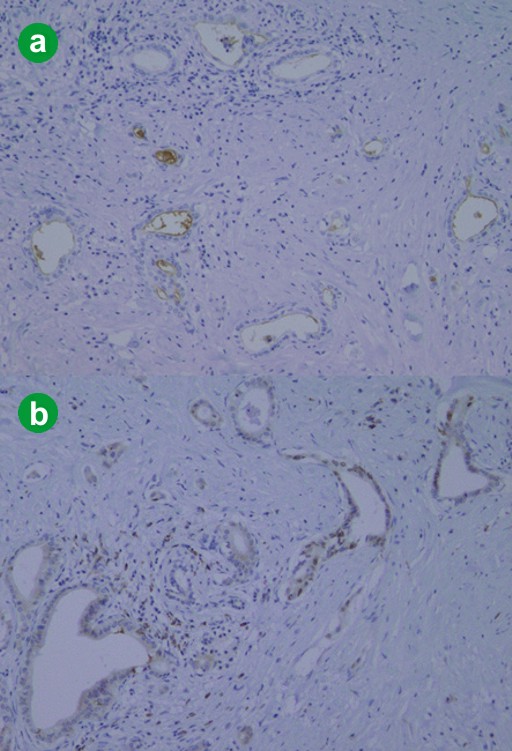

Figure 5. a. Immunolabeled features of the tumor showed focal positive-labeling for MUC1/DF3 mainly at the cell membrane (x100). b. Diffuse positive labeling for Smad4 mainly at the cytoplasm and focally nucleus are also seen (x100). |

In this study, we carried out immunolabeling for p16, p53, Smad4, and MUC1 to clarify the stage of genetic progression of this minute pancreatic ductal adenocarcinoma. Inactivation of the p16 function in pancreatic ducts is considered to be an early event in the genetic progression of carcinogenesis [7]. On the other hand, inactivation of p53 and Smad4 are considered to be late events [4, 5, 6]. Maitra et al. reported that loss of the p16 function is found in low-grade PanINs with a frequency of up to approximately 95% in invasive pancreatic ductal adenocarcinoma [4]. Nuclear overexpression of p53 protein and loss of DPC4 expression are found only in PanIN-3 (with frequencies of 57% and 28%, respectively) and invasive pancreatic ductal adenocarcinoma (50-75% and 55%, respectively) [4]. On the other hand, MUC1 is one of the representative surface markers of a pancreatic ductal adenocarcinoma [10], and Ueda et al. reported that MUC1 is the most sensitive and specific marker for invasive pancreatic carcinoma [11].

In light of these immunohistochemistry results, focal positive labeling for MUC1 in various duct lesions suggested that all duct lesions within the tumor area did not have sufficient malignant potential. On the other hand, no expression of p16, p53 and Smad4 suggested that the genetic abnormalities of early events, such as p16 inactivation, had occurred, but that late events, such as p53 or Smad4 inactivation, had not occurred sufficiently. In other words, these duct lesions within the tumor area might be a state where precancerous lesions and cancerous lesions coexist.